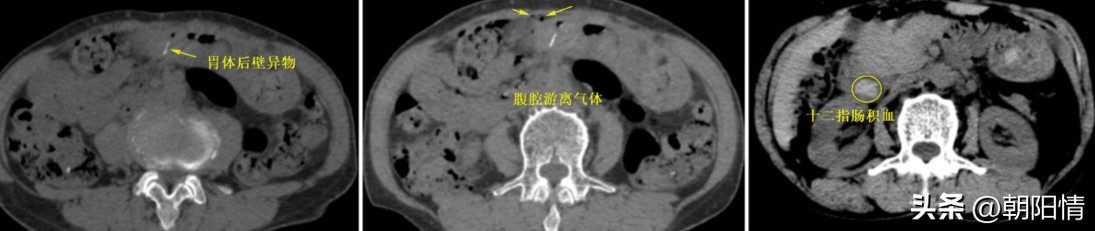

Case5:老年女性,突发腹痛入院。胃异物合并胃穿孔、腹腔积气、十二指肠积血。